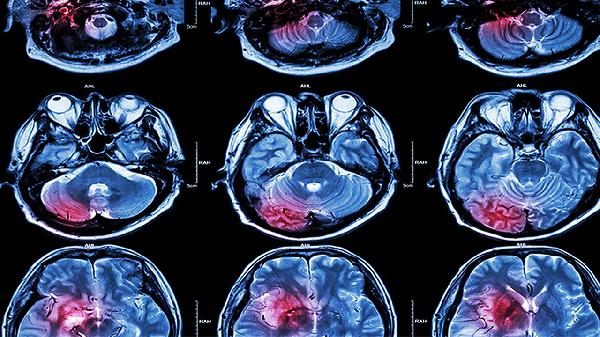

基底节区脑梗死患者需长期控制血压、血糖、血脂等危险因素。饮食应低盐低脂,适量补充优质蛋白和膳食纤维。戒烟限酒,保持规律作息。康复期可进行散步、太极拳等有氧运动,每周3-5次,每次30分钟。定期复查头颅CT或MRI,监测病情变化。出现头痛加重、意识障碍等异常情况需立即就医。